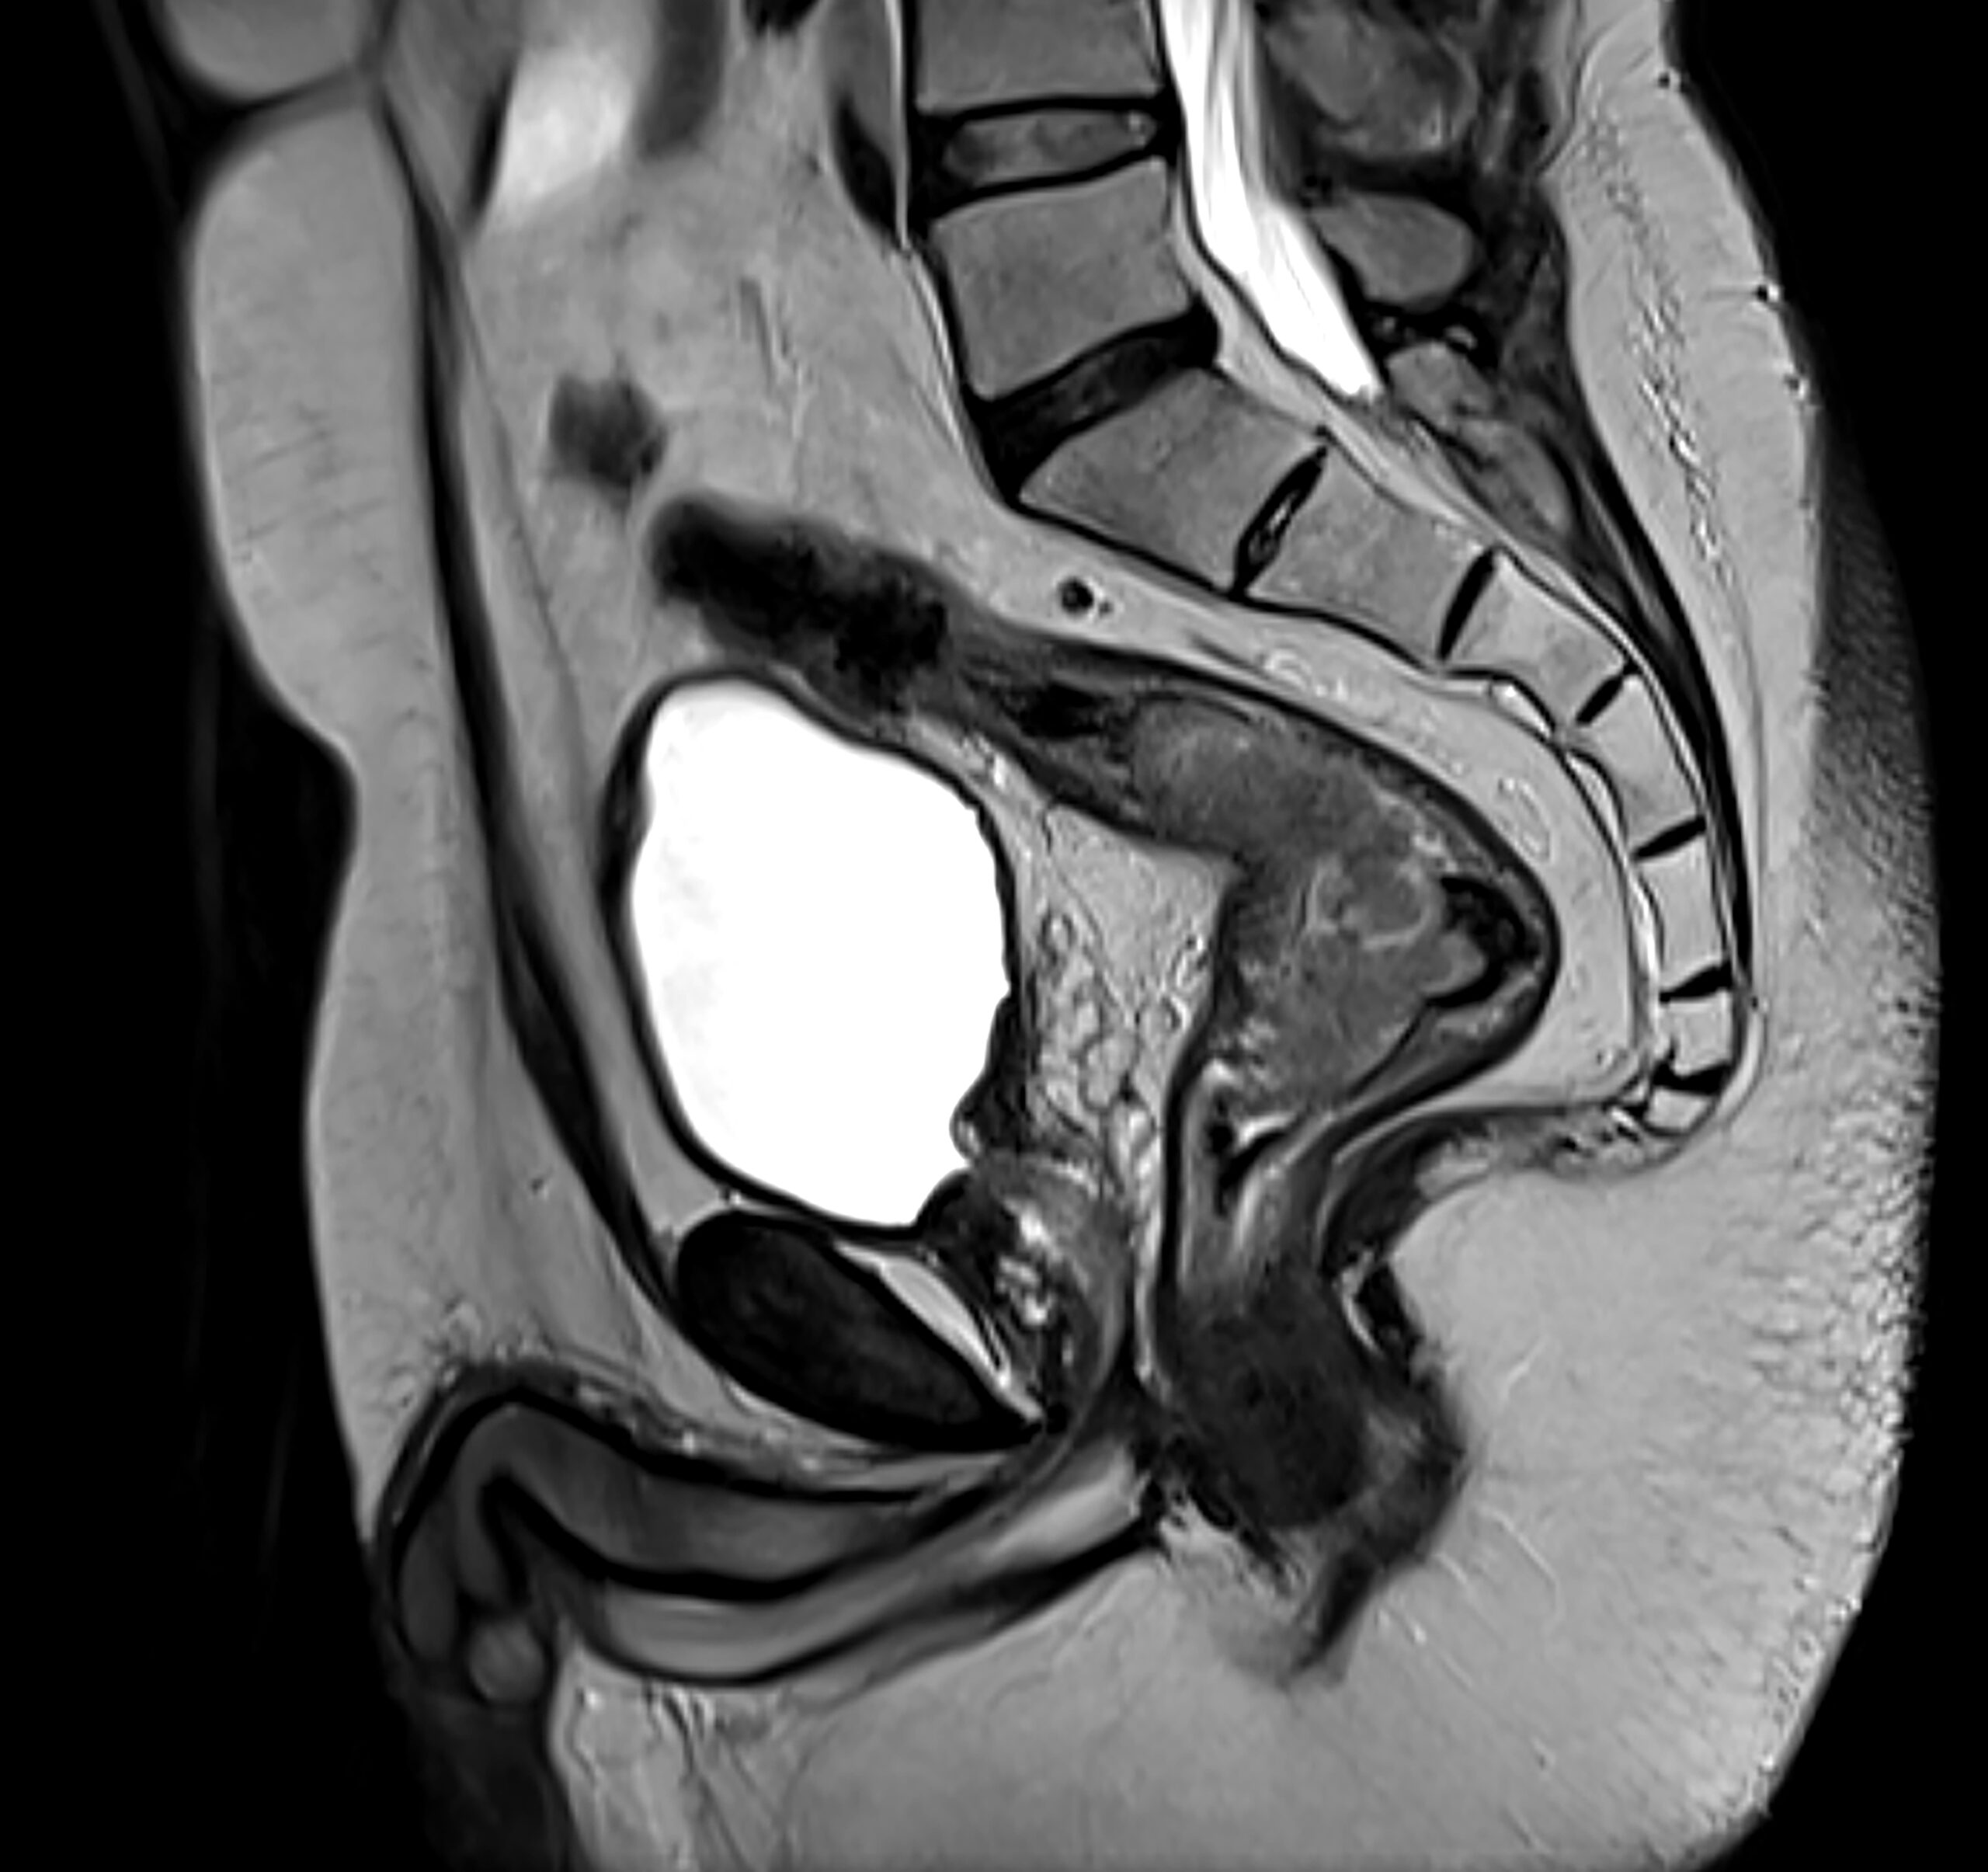

MRI image of colorectal cancer. Source: Getty.